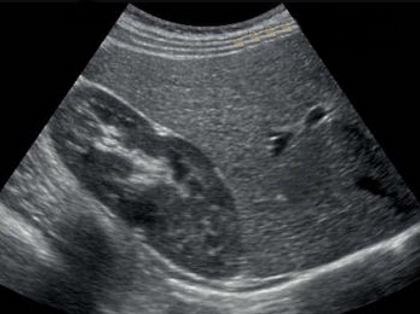

Una ecografía es un examen médico que uiliza un transductor para capturar imágenes en vivo desde el interior de su cuerpo mediante ondas sonoras de alta frecuencia.

La ecografía le permite al médico ver problemas con órganos, tejidos y vasos sin necesidad de efectuar una incisión.